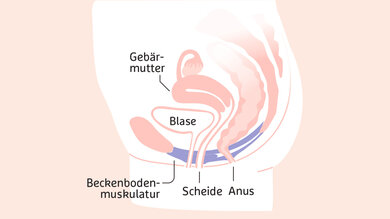

Beckenboden

Der Beckenboden ist die Muskelplatte zwischen Scham- und Kreuzbein, die unter anderem die Schließmuskulatur der Harnröhre und des Afters unterstützt. In der Schwangerschaft und erst recht bei der Geburt wird das Gewebe stark gedehnt. Nach der Geburt kann es deshalb sein, dass Urin in die Hose geht. Oder die Frauen spüren den Harndrang erst spät. Je nachdem, wie die Geburt verlaufen ist, kann das auch den Darm betreffen. Keine Panik: In den allermeisten Fällen stabilisiert sich der Beckenboden wieder. Dafür braucht er erst mal vor allem: Entlastung. Susanne Huhndorf empfiehlt deshalb Ruhe – am besten im Liegen: „Die Zeit nach der Geburt heißt nicht umsonst Wochenbett.“ Schon währenddessen können Frauen in der Regel kleine Übungen machen, um wieder ein Gefühl für die Beckenbodenmuskulatur zu bekommen. Fragen Sie Ihre Hebamme. Gezielt trainiert wird nach dem Wochenbett im Rückbildungskurs.